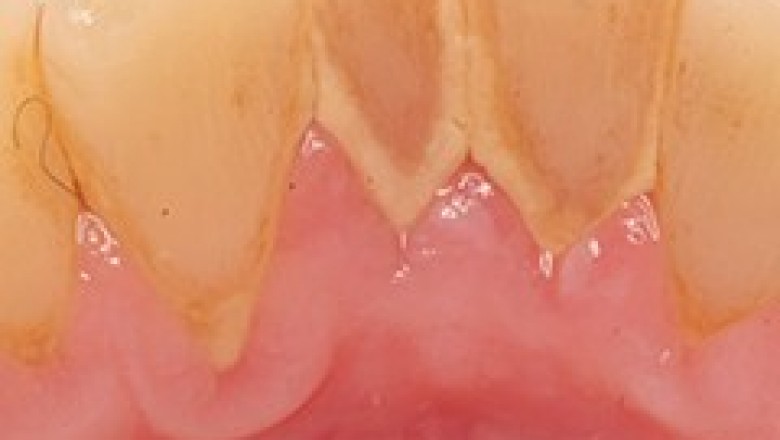

Tartar is the hard calcified material that builds up on teeth. It is formed mainly from minerals in saliva mixed with the bacteria of dental plaque. It can only be removed by a dental professional. We provide Emergency Dental Services in Mount Prospect like Abscess-Gum & Dental Abscess, Calculus Teeth, Chipped Tooth, Erosion, Fillings, and Gum Disease, Jaw Injury, Periodontitis, etc. Contact us at 847-728-8417 for more information.